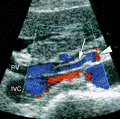

- Diaqnozu dəqiqləşdirmək üçün Qc venaları yoxlanılmalıdır. Bunun üçün dopler USM, KT-angioqrafiya, MRT-angioqrafiyalar və ya kontrastlı venoqrafiya edilir.

- Görüntüləmədə Qc venalarının trombotik tutulması diaqnozu dəqiqləşdirən əlamətdir.

- Doppler USM;

- KT-angioqrafiya;

- MRT-angioqrafiya;

- Kontrastlı venoqrafiya;

Qaraciyər venalarının görünməməsi, kontrastlaşmaması və ya trombla tıxanması.